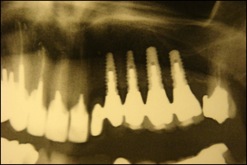

Après quatre à 6 mois l’os est complètement soudé et les implants peuvent être posés.

Photos implants dans greffe osseuse